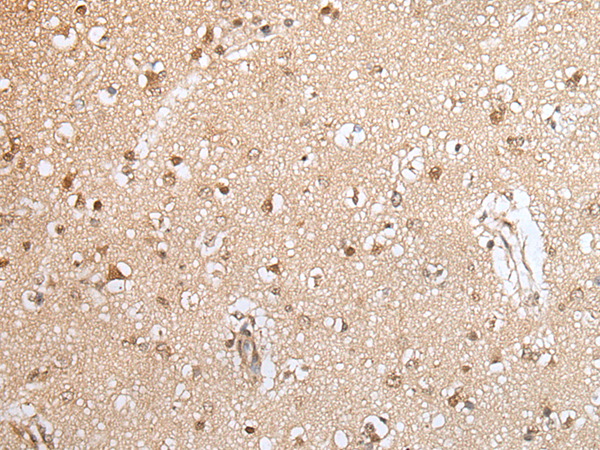

IHC positive control: |

Human esophagus cancer and human brain |

IHC Recommend dilution: |

25-100 |